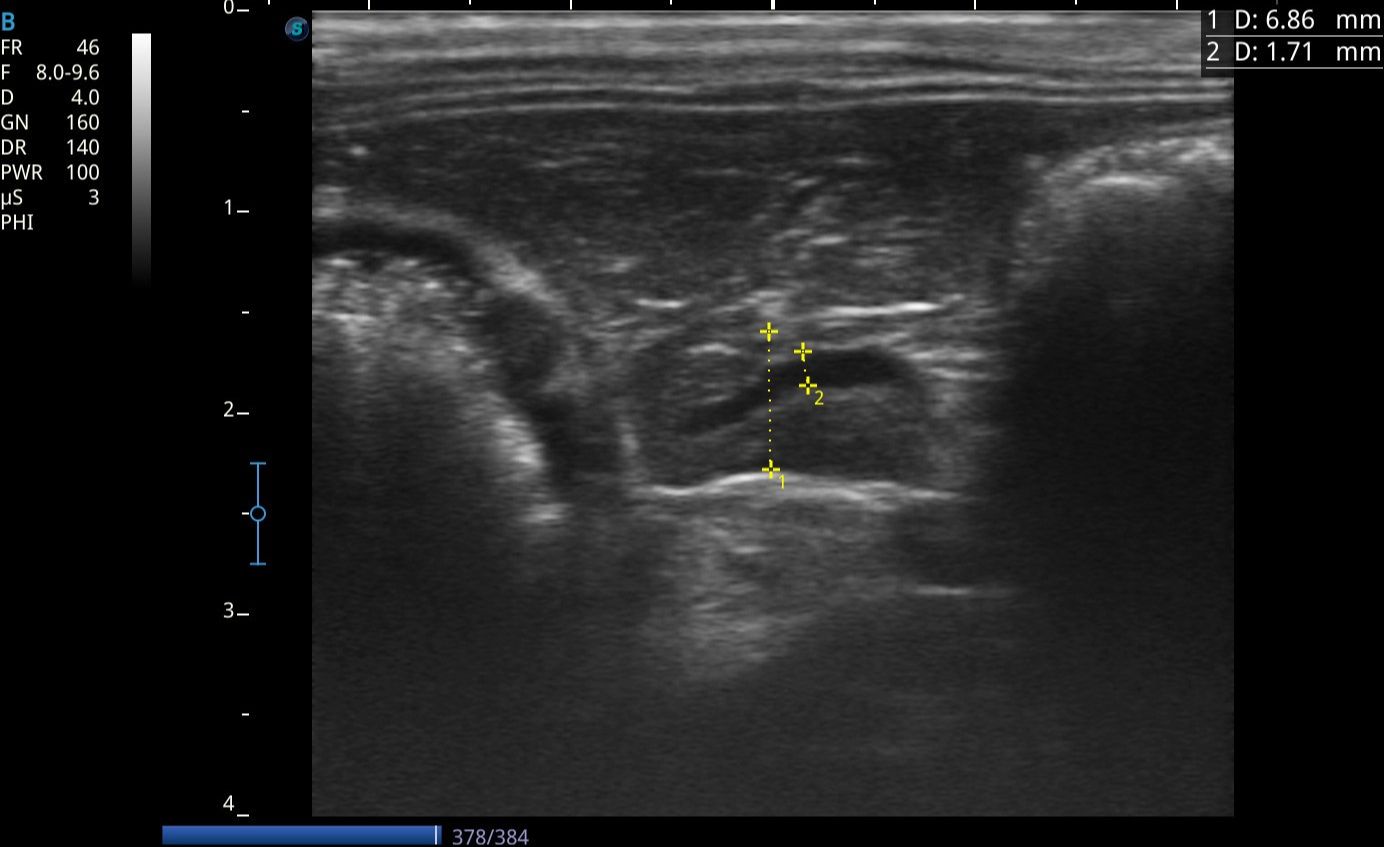

Images from the X5V